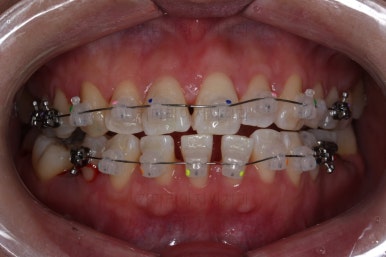

1. 초진

초진 시 입안의 모습입니다.

당장 눈에 띄는 부분은 아래 앞니 사이에 틈새가 있어 치석도 많이 쌓여있는 상황이고요.

윗니-아랫니를 각각 보면 치아가 썩고 부러져 뿌리만 남은 치아가 많이 보입니다.

남은 치아들도 곳곳에 충치가 보이고요.

또 전반적으로 앞니가 앞으로 밀려나와 뻐드러져 있는 모습도 관찰되네요.